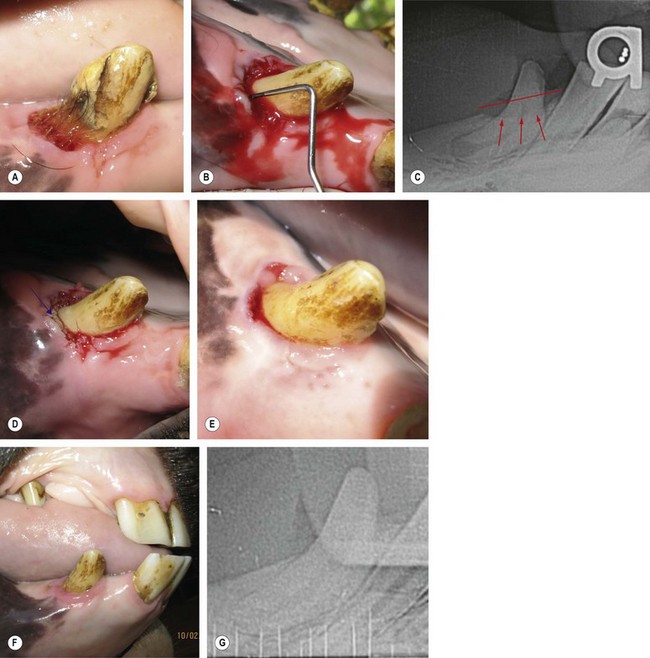

In cases of Stage 2 periodontitis (up to 25 % attachment loss),61 local antibiotic administration (LAA) may be indicated as an ancillary treatment after completion of pocket debridement and irrigation. In human dentistry, tetracycline impregnated fibers and doxycycline, minocycline, and metronidazole gels are commercially prepared for LAA. A biodegradable, polymerized 8.5 % doxycycline gel (Doxirobe Gel)g is labeled for veterinary use in dogs and has been empirically used in other species, including horses (Fig. 21.18). Doxycycline has a broad spectrum of antibiotic activity against several known bacteria associated with periodontal disease, and the degradation of doxycycline gel provides localized, sustained release of antibiotic for approximately 2 weeks. Additionally, doxycycline binds to dentin, cementum, and bone for prolonged antibiotic release, inhibits the collagenase enzyme (an enzyme that slows the healing of the periodontal tissues), and stimulates fibroblast activity to re-establish the periodontium.62,63 The polymer gel also provides a physical barrier for reinfiltration of food and debris into the periodontal pocket, which is an important goal in the treatment of cheek tooth periodontal disease. Although the use of LAAs has become a popular practice in equine dentistry, this ancillary procedure has received no critical evaluation and, in the authors’ opinion, has limited indications in the equine patient. Other less expensive materials have shown clinical effectiveness as temporary barrier materials (e.g., impression materials, calcium sulfate, calcium alginate).

image

Fig. 21.18 Application of a local antibiotic (perioceutic). (A & B) A 12-mm periodontal pocket (PP) on the vestibulodistal aspect of the right mandibular canine tooth (404) of a young gelding. (C) Radiographs reveal horizontal bone loss of the associated alveolar bone (Stage 2 periodontitis). (D) The blue arrow shows the applied Doxirobe Gel in the PP. (Note that the perioceutic material fills the entire pocket.) (E) At the 2-week follow-up visit, the PP depth measured 4 mm. (F & G) At the 6-month follow-up visit, probing of the PP produced negligible depth and radiographs revealed alveolar bone regrowth.